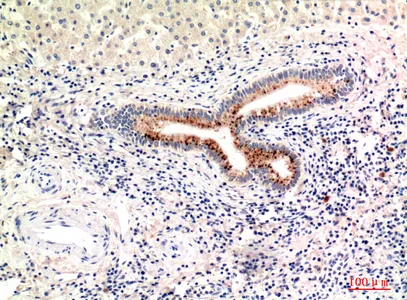

Collagen V alpha 2 Rabbit Polyclonal Antibody

Cat: APRab00499

Size1:50μl Price1:$150

Size2:100μl Price2:$280

Size3:500μl Price3:$1200

Size2:100μl Price2:$280

Size3:500μl Price3:$1200